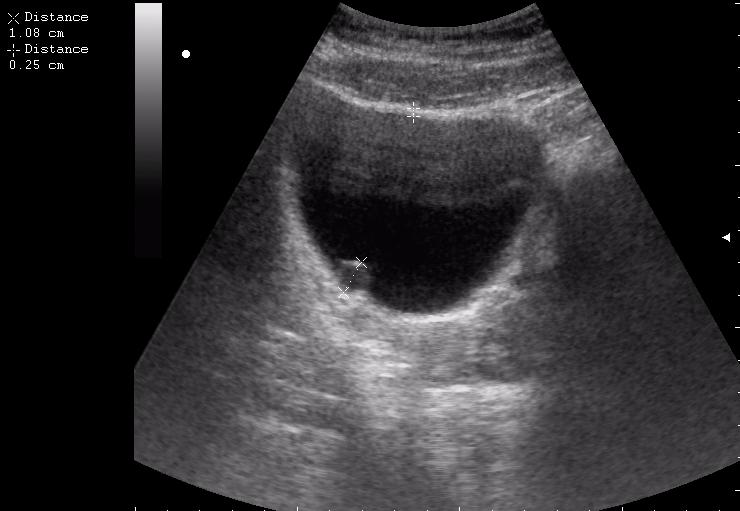

Сравните

Продольное сканирование мочевого пузыря После легкой перкуссии мочевого пузыря

зато какое наполнение! а осадок убедительный! а же не 7-кой смотрела!На сонограммах неубедительно продемонстрирован осадок да и стенки м.п. не утолщены.

Богу богово, кесарю - кесарево (я про анализы и клинические данные). На сонограммах неубедительно продемонстрирован осадок да и стенки м.п. не утолщены.